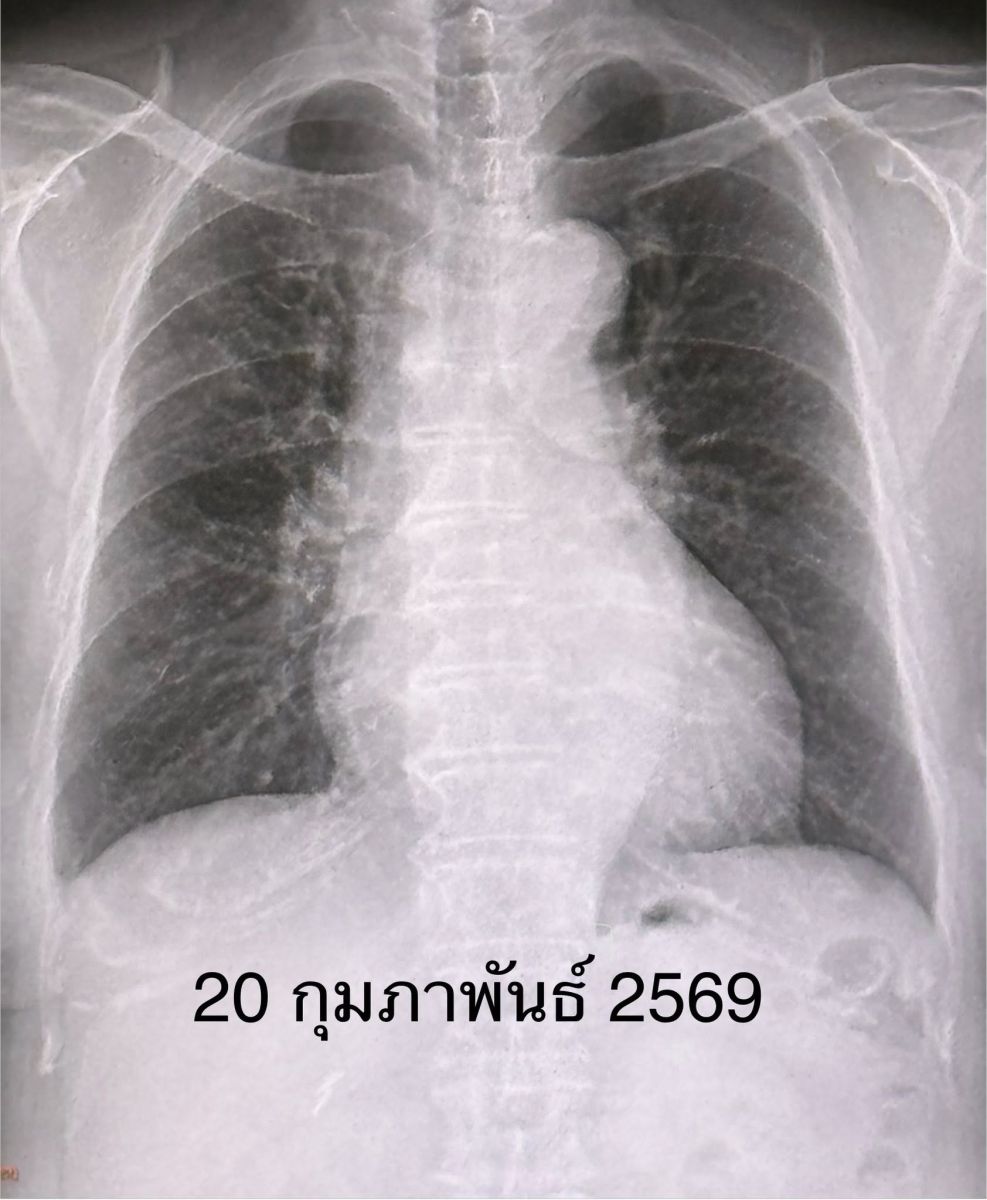

ผลตรวจร่างกาย ไม่มีไข้ ระดับออกซิเจนที่ปลายนิ้ว 96% หัวใจเต้นเร็ว 130 ครั้ง/นาที หัวใจเต้นผิดจังหวะ ฟังปอดปกติ ทำคลื่นไฟฟ้าหัวใจ พบหัวใจห้องบนเต้นระรัว (Atrial fibrillation) ตรวจหัวใจดัวยคลื่นเสียงความถี่สูง (Echocardiogram) ไม่พบความผิดปกติ เจาะเลือด เม็ดเลือดขาวในเลือดปกติ ส่งเลือดเพาะเชื้อ ไม่ขึ้นเชื้อแบคทีเรีย เอกซเรย์ปอด มีฝ้าขาวลักษณะคล้ายก้อนที่ปอดข้างขวากลีบบน แยงจมูกส่งตรวจสารพันธุกรรม RT-PCR พบเชื้อโบคาไวรัส (Bocavirus)

เคสนี้แพทย์วินิจฉัย ว่า โบคาไวรัส (Bocavirus) ทำให้เกิดปอดอักเสบ และภาวะหัวใจห้องบนเต้นระรัว (Arial fibrillation) ในผู้สูงอายุรายนี้ ซึ่งมีโรคประจำตัวเบาหวาน และไขมันสูง หลังให้ยา cordarone หัวใจกลับมาเต้นเป็นปกติ ให้การรักษาตามอาการ ไอลดลง ไม่มีเสมหะ ไม่มีไข้ ติดตามเอกซเรย์ปอดกลับมาปกติในเวลา 6 วัน